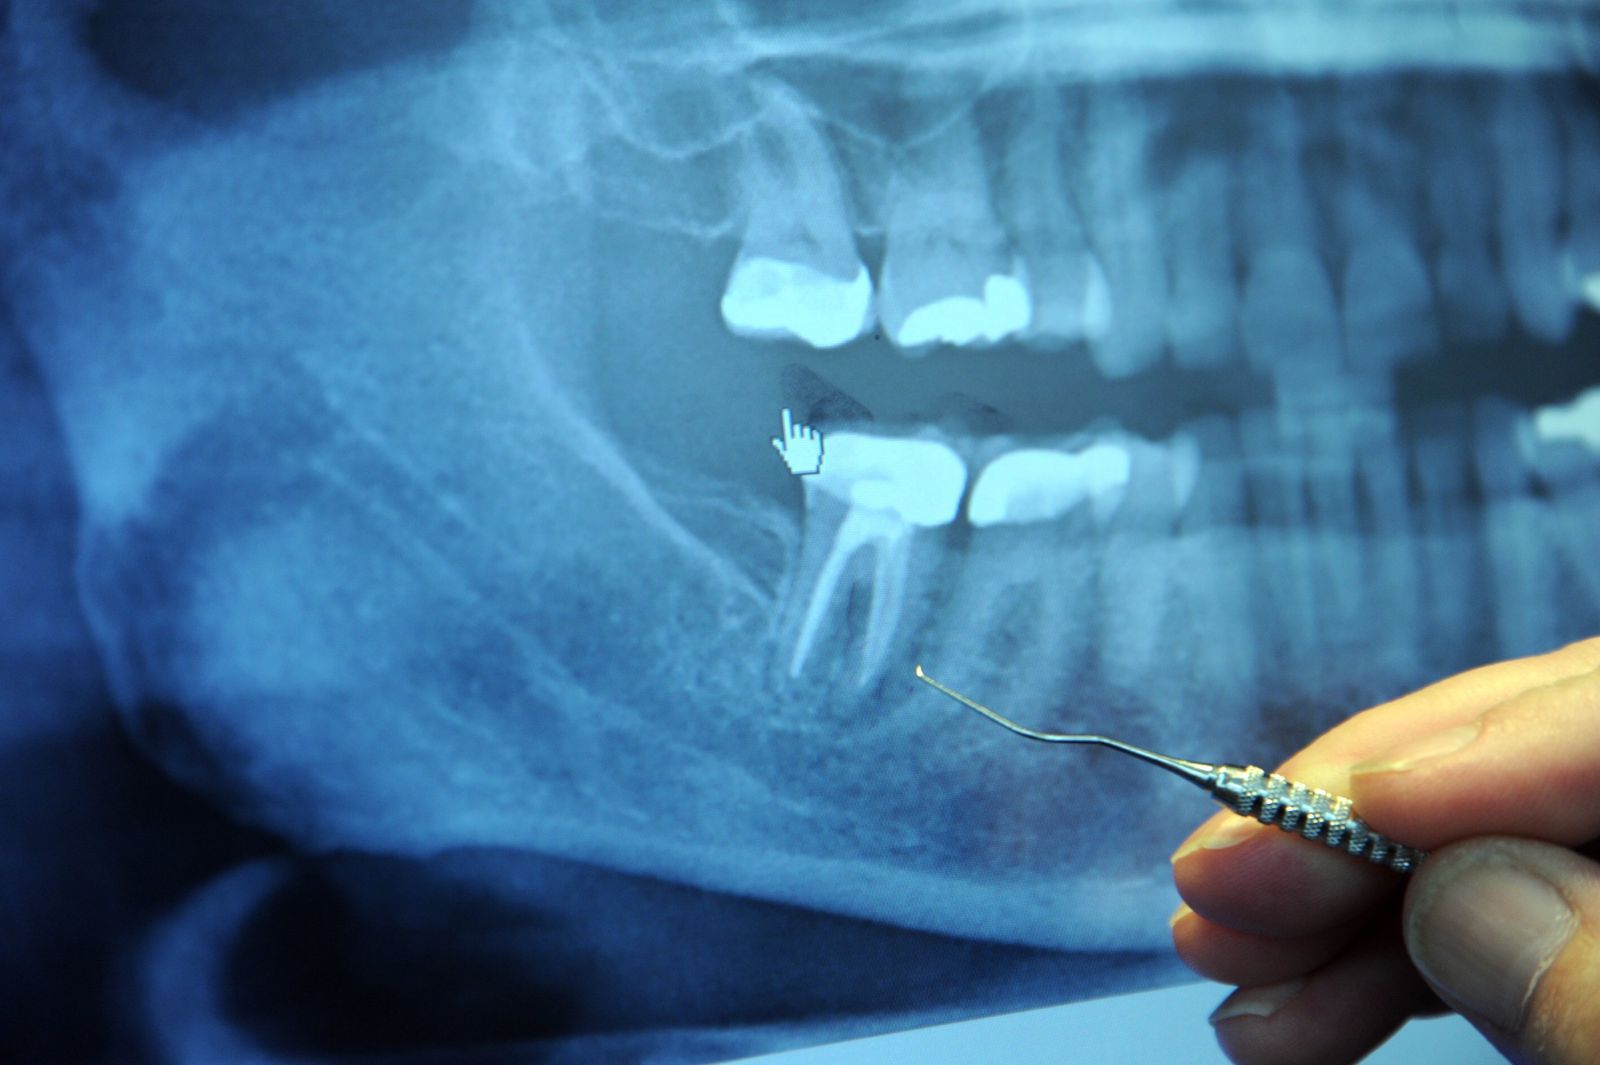

- Chụp X-quang răng

Hình ảnh phim X- quang bị viêm tủy răng